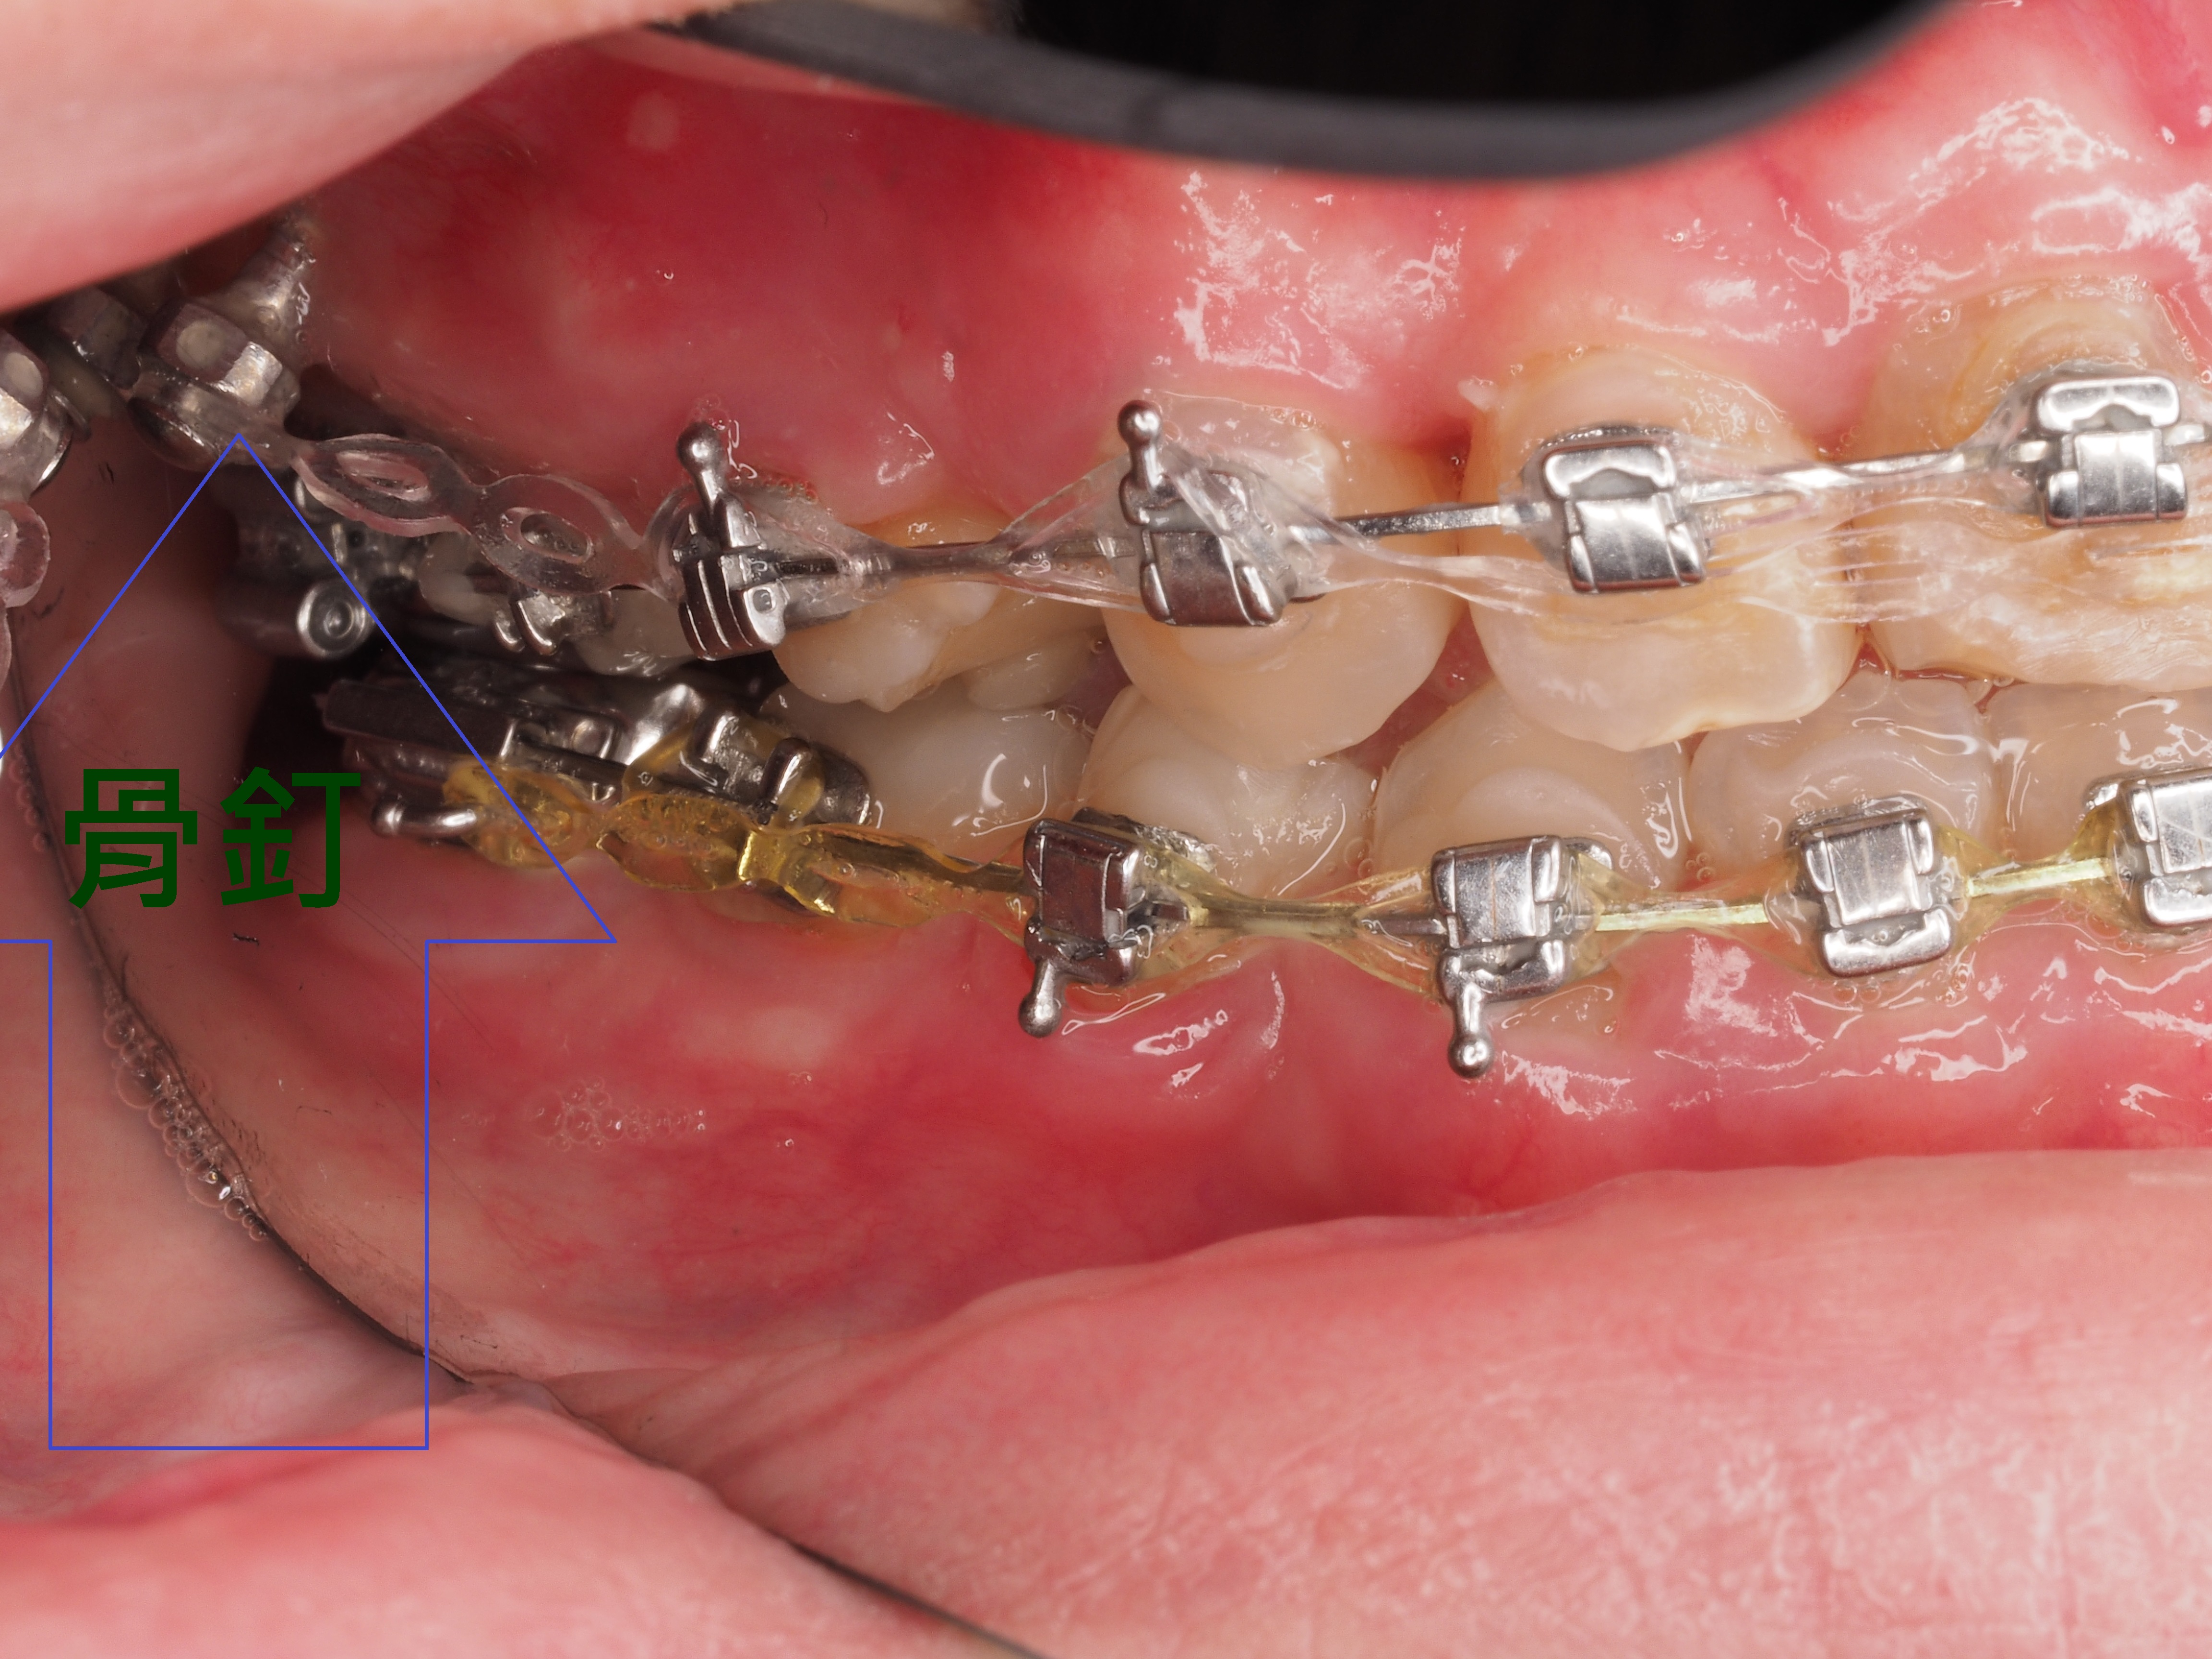

患者牙齒凌亂虎牙外暴大大影響外觀,並造成清潔不易、蛀牙、牙齦發炎等問題,透過醫師矯正評估分析建議矯正計畫內容包含拔牙、放置迷你螺絲(骨釘)等步驟,將原本凌亂外暴的虎牙歸位,改善咬合使發音更清晰,咀嚼效率更好,大幅改善清潔困擾,使日常刷牙及使用牙線清鬆有效率。

3.拔牙與骨釘:為騰出空間進行矯正,需要拔牙;骨釘用於輔助移動牙齒,初期可能會有異物感,但通常很快能適應。(下兩圖)

拔牙後放骨釘關閉空間原理與優點:

1.骨釘是植入在骨頭中的支撐點,提供穩定的錨定力量,確保牙齒移動的方向不受影響。

2.傳統矯正中移動牙齒可能造成其他牙齒跟著移動,使用骨釘可以精準控制牙齒的移動方向,讓拔牙後的縫隙能有效且正確地關閉。

3.骨釘可以大幅提升牙齒移動的效率,可能縮短矯正療程時間。

4.除了關閉拔牙空間,骨釘還能應用於骨性暴牙、嚴重深咬等情況,讓治療範圍更廣。

虎牙(犬齒)暴牙缺點(上左右2圖):

口腔清潔困難:虎牙暴牙形成清潔死角,易積聚牙菌斑和牙結石,增加蛀牙、牙周病風險。

影響咀嚼與咬合:犬齒主要功能是撕裂食物,位置不對會影響咬合功能,使食物難以充分咀嚼。